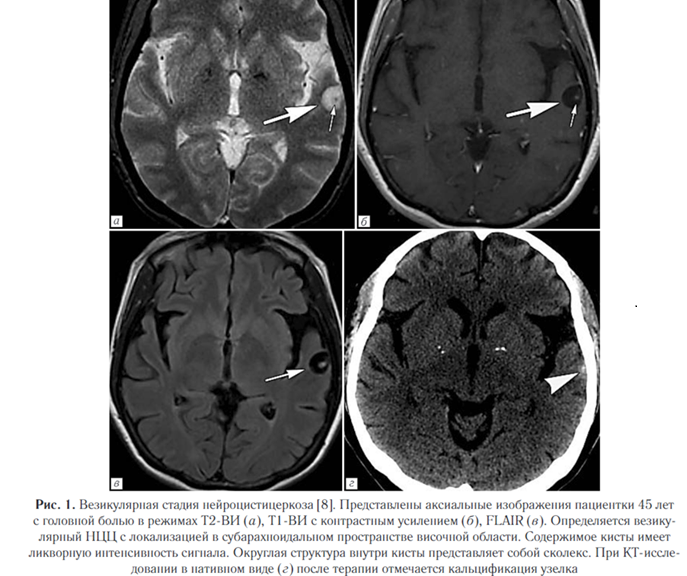

Субарахноидально-цистернальный НЦЦ поражает субарахноидальные пространства и прилегающие мозговые оболочки, которые представляют собой наиболее распространенную локализацию паразитов (рис. 4).

Проявляется в виде объемных поражений, которые могут стать причиной гидроцефалии (состояние может быть вторичным по отношению к базилярному арахноидиту).

Кисты также могут вызывать отек прилегающего вещества мозга с глиозом и васкулитом [8]. Внутрижелудочковый нейроцистицеркоз. Составляет от 0,7% до 33% всех случаев НЦЦ, часто сочетается с субарахноидальным.